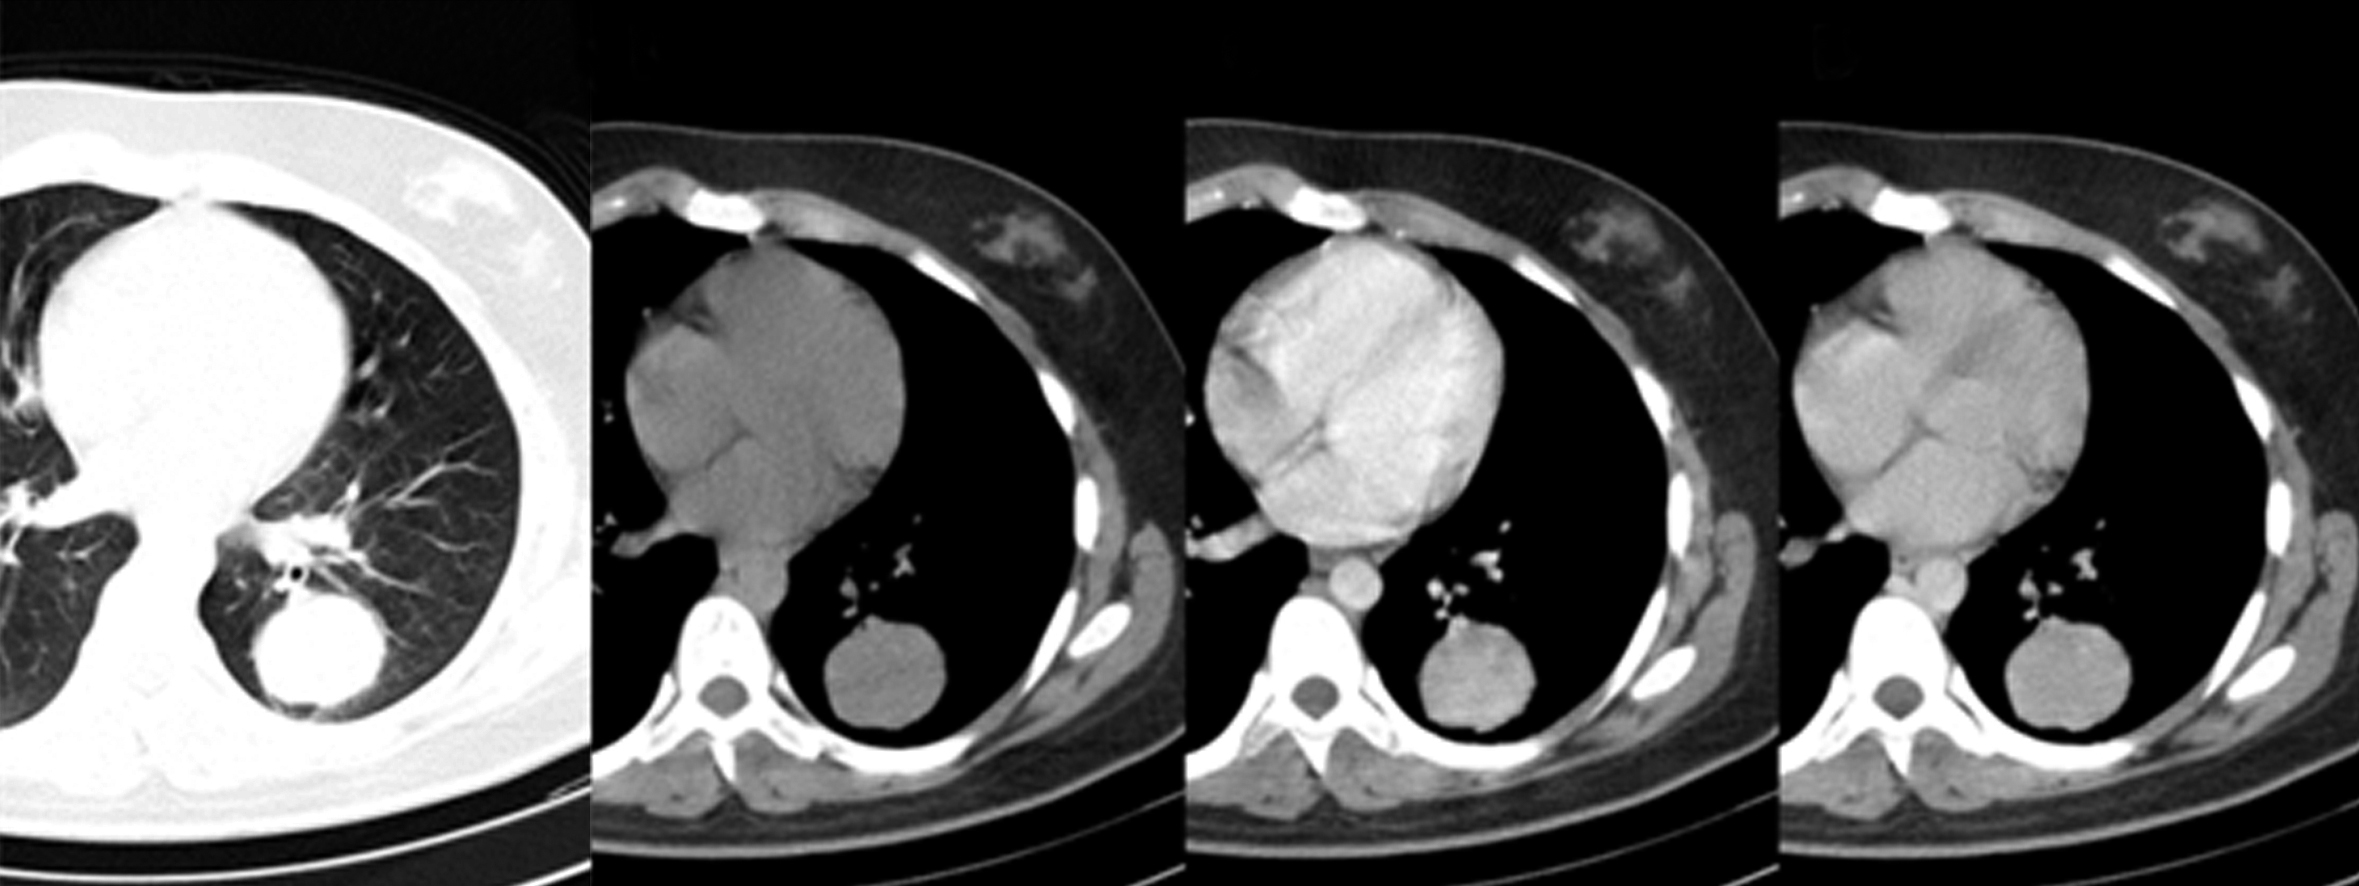

Dados los hallazgos radiográficos se solicita tomografía computarizada de tórax. Se realizan adquisiciones sin y con medio de contraste intravenoso, en tiempo arterial y venoso. Se observa en el segmento apical del lóbulo inferior izquierdo una imagen sólida, redondeada, de bordes lisos y bien definidos, de 42 mm de diámetro, con pequeña calcificación en el sector inferior y realce homogéneo con el medio de contraste. No se observan otras alteraciones de la densidad del parénquima pulmonar, no hay derrame pleural, pericárdico, adenomegalias hiliomediastinales ni axilares. (Figura 2)

Figura 2

TC con ventana de pulmón (a) donde se observa masa en hemitórax izquierdo rodeada de parénquima pulmonar sano. TC sin contraste intravenoso (b), en tiempo arterial (c) y en tiempo venoso (d) donde se observa el realce homogéneo.

Tras los hallazgos radiológicos, se solicita tomografía computarizada de tórax, que se realiza sin y con medio de contraste yodado por vía intravenosa (Figura 5), en la que se observa masa ovoidea de 50 x 43 mm en lóbulo medio y segmento anterior de lóbulo inferior, bien delimitada, de densidad heterogénea con pequeño sector cavitado y discreto realce periférico tras la administración de medio de contraste. No se observan otras lesiones en el parénquima pulmonar, pleura, mediastino ni adenomegalias.

Figura 5

TC de Tórax: cortes axiales en ventana de mediastino previo a la administración de contraste (a), en fase venosa (b) y con ventana de pulmón (c.); en el lóbulo medio y segmento basal anterior del lóbulo inferior derecho se observa masa ovoidea, bien definida, de densidad heterogénea con realce periférico y un pequeño sector cavitado.